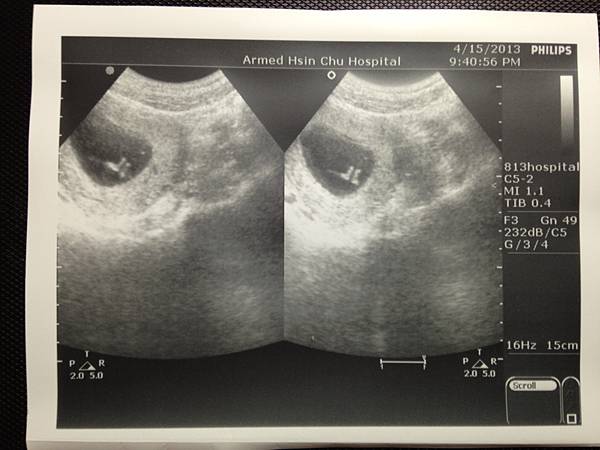

(這是果然有小朋友的樣子了耶)

你現在有4.67cm嚕

心跳164下, 大約是11週3天

可是個有頭有臉的小傢伙, 還看得到你的雙腳呢!

(小腳丫併在一起的感覺好可愛呦!)